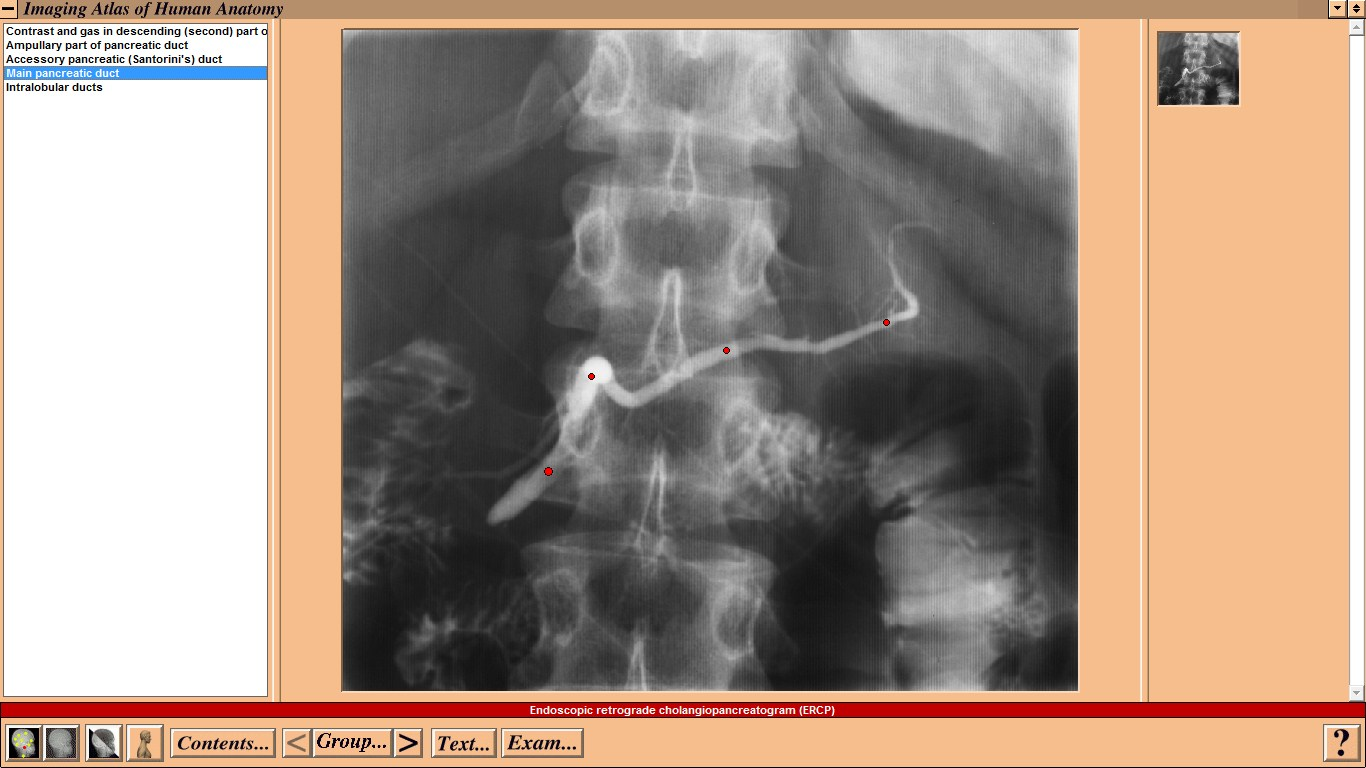

Windows Совместимость с Vista: неизвестно Системные требования: IBM or compatible PC, 486SX, 8MB RAM, 640 × 480 display, 256 colors, double speed CD-ROM drive, Microsoft Windows 3.1 or later, optimum: Pentium processor, 800 × 600 display, more than 256 colors, ISBN 0-7234-2187-0, St Louis, Mo, Mosby, 1995 Язык интерфейса: только английский Таблэтка: Не требуется Описание: This CD-ROM provides a detailed atlas of radiologic anatomy in all forms, including plain films, magnetic resonance (MR) imaging, computed tomography (CT), venography, and angiography. It is formatted to present a concise atlas, cephalad (skull) to caudad (feet). The disc is easy to work with, and I did not have any trouble setting it up. The graphics and table of contents are laid out well. Navigating the various parts is relatively simple. The opening graphics are well displayed, allowing instant access to pictures or the table of contents; therein lies the simplicity of finding an anatomical part of the body to review. Each screen contains a picture of the radiograph accessed, key landmarks (with a glossary that can be turned off), related slides that can easily be accessed, and a self-exam. Диск содержит более чем 3500 радиографических изображений нормальной анатомии, включая обычные рентгенограммы, КТ, МРТ, ангиограммы, артериограммы и видео УЗИ. Исчерпывающий уровень анатомических ориентиров с возможностью самоконтроля. Издание рассчитано прежде всего на рентгенологов. Доп. информация: Поскольку издание старое, придется установить древнюю версию Quick Time - 2.0.3.51 (есть на самом диске). Набор в группу «Хранители» - Помогите сохранить редкие раздачи Программы и Дизайн » Системы для бизнеса, офиса, научной и проектной работы » Медицина - интерактивный софт